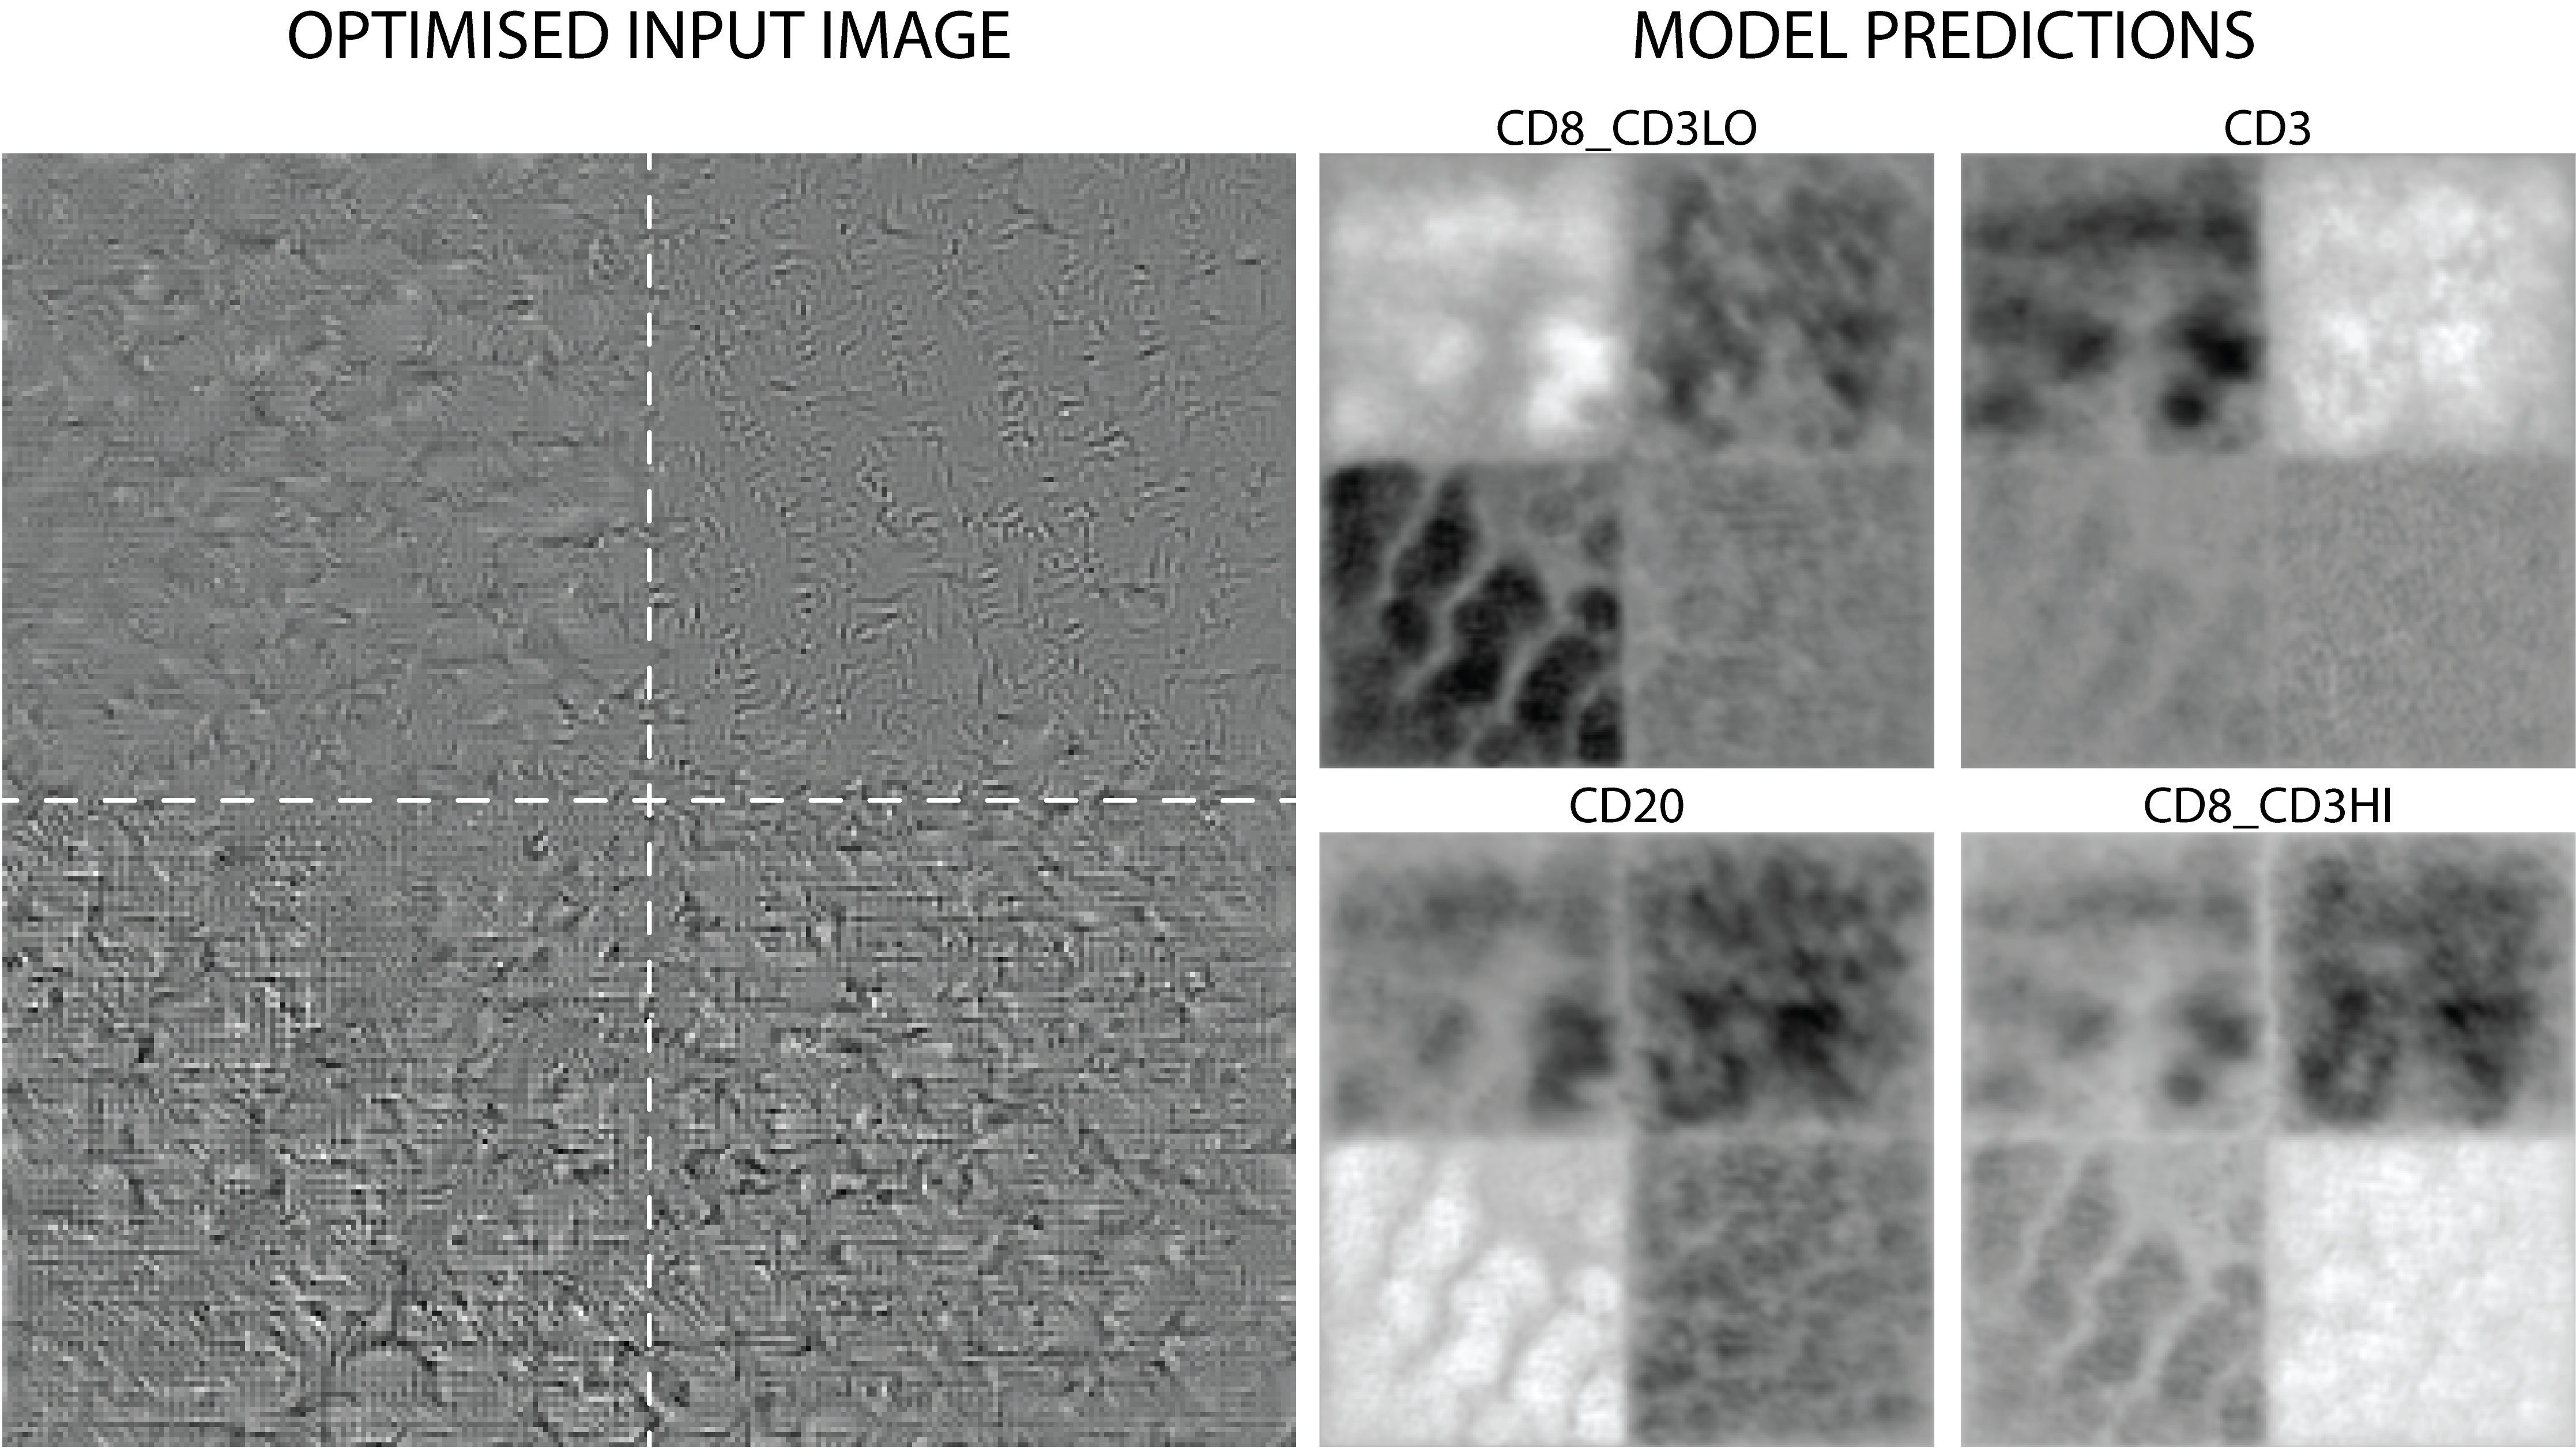

To explore how the network is able to distinguish between different lymphocytes so successfully, we use stochastic gradient descent (SGD) to optimize an input image set uniformly to the normalised mean of all training set images to maximise output logits (raw outputs, without activation or normalisation) for each class, as proposed by Simonyan et al. [28]. We extend this technique for multi-class segmentation using a custom loss function designed to balance per-class optimisation for class-specific quadrants in a single image, allowing for easy comparison of learned features.

5.1 Feature Visualisation

For input image optimisation we used a learning rate of 1.0 and ran SGD for 10,000 steps. We optimise each quadrant for a different positive class (i.e. those classes not consisting of background or cells outwith our classes of focus), by specifying a mask of dimension (where is the and dimension of the input image – in this case 256 pixels – and is the number of positive classes – in this case 4) such that for each class a different quadrant is set to ones, and the remaining elements in to zero – the objective being to maximise the model outputs for each class in a specific region, as shown in Figure 3. This mask is used to separate pixels to maximise and those to minimise in the model outputs according to class. The Rectified Linear Unit (ReLU) is applied to the regions to minimise, to control for disproportionate minimisation of negative regions in preference to the positive regions, in which we are interested. We also use a regularisation term consisting of the variance between positive class outputs to ensure that the input is not disproportionately maximised for classes associated with simpler features, as shown below. Simonyan et al. included an additional regularisation term for the input image to counteract over-optimisation for a single feature, but in practice we found that this lead to negligible change in output and so we omit it – likely this omission is possible because we are optimising for mean pixel classifications and thereby for multiple features, rather than for a single label.

As shown in Figure 3, the results of this experiment show that the model has learned textural features of the nuclear chromatin to discriminate between different classes, as the predominant difference between regions is textural and evident features are small. This difference in texture is particularly pronounced between CD8_CD3LO and CD3 only expressing cells, with the CD3 only class quadrant in particular optimising for quite small, curved features. In models like ours where the output class probabilities for each pixel are calculated – and thereby constrained and exaggerated – through use of softmax as an output function, it is difficult to differentiate a strong positive signal for an individual class from a strong negative signal for the other classes. This also holds for the logits which we here hope to maximise for each class – in the context of actual predictions by the model, these logits would be passed into a softmax function, and as such interact in a way we so not visualise here – for example, classes A and B may have a high logit output, but if A is lower than B, the softmaxed output will strongly favour B even if the raw difference in output was not great. This makes optimisation-based visualisation of features in this way problematic: if we optimise for softmaxed outputs, the output is quickly saturated and the inputs are unintelligible, but if we optimise for logits, we do not accurately represent the actual classifications of the entire model.